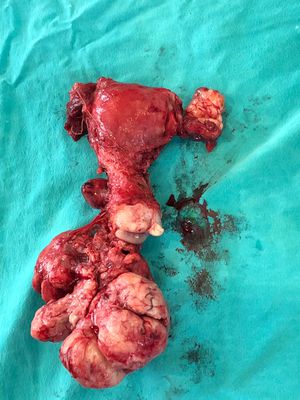

Not cervical cancer. Jeez. A tumour in the cervix that size and with infiltration of vaginal cupula wouldn't be operated on. Anyway. This is either a terrible polyp or a multilobulated pedunculated fibroid tumor of the uterine neck. It's exact point of origin isn't well defined. it may also be ovarian mass if it is that the right ovary is behind the uterine body. But the surgeon probably left that ovary in the woman so as to not abate her lady hormones.